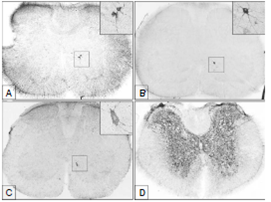

La primera evidencia de la presencia de antígenos de la rabia en la médula espinal se observó a las 24 horas después de la inoculación. Estos se manifestaron como pequeñas inclusiones dentro del asta ventral de la médula lumbar, con ubicación ipsilateral a la extremidad posterior inoculada, a nivel de los segmentos L5-L6 (figura 1A). Partículas como estas no se observaron en ninguno de los dos tipos de controles, como tampoco en segmentos más caudales de la médula espinal de los animales infectados.

A las 32 horas después de la inoculación se hicieron visibles las primeras neuronas que contenían antígeno suficiente para demarcar la morfología completa de las células (pericarion y dendritas). Estas se localizaron en el asta ventral de la médula lumbar ipsilateral, entre los segmentos L5-L6, dentro del grupo de núcleos neuronales de la lámina 9 (figuras 1B y C), en la misma ubicación en la que previamente, a las 24 horas después de la inoculación, se habían observado los primeros antígenos.

A las 48 horas después de la inoculación, el virus se había dispersado a otras neuronas dentro de la sustancia gris de los dos lados de la médula lumbar (L3-L6) (figura 1D).

A las 40 horas después de la inoculación se observaron las primeras neuronas inmunorreactivas al virus, en la médula torácica ipsilateral al miembro inoculado, localizadas en la región medial de la sustancia gris, en un área correspondiente a la lámina 8 (núcleo 8Sp) (figura 2A), a nivel de los segmentos T11-T13.

A las 48 horas después de la inoculación se reveló la presencia de las primeras neuronas inmunorreactivas en la médula cervical correspondiente a los segmentos C4-C6. Estas se ubicaron también en la zona medial ipsilateral al sitio de inoculación, dentro de la lámina 8 (figura 2B y C).

A las 56 horas después de la inoculación se observaron neuronas inmunorreactivas dispersas en la sustancia gris de los dos lados de la médula cervical.

Apenas a partir de las 96 horas de la inoculación de este experimento, se observaron los primeros signos que consistían en parálisis parcial de las extremidades posteriores. En la fase terminal de la enfermedad (a partir de las 120 horas de la inoculación), los animales estaban completamente postrados, sin movimiento alguno. La inmunorreacción en todos los niveles de la médula espinal exhibió una densa concentración de antígenos virales en la sustancia gris (figura 2D). En las figura 3 y 4, se resumen esquemáticamente los procesos de dispersión y ascenso del virus dentro de la médula espinal.